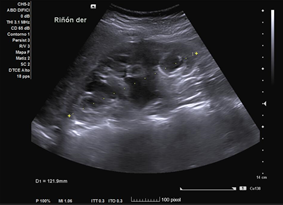

En ecografía clínica desde el centro de salud, se objetiva gran dilatación del sistema excretor del riñón derecho, con adelgazamiento de la cortical (hidronefrosis grado III-IV). No se aprecia litiasis u otra causa obstructiva a nivel renoureteral ni vesical. Riñón derecho conserva tamaño normal. Riñón izquierdo de tamaño y ecoestructura normales, sin dilatación piélica. Vejiga bien replecionada sin alteraciones en su pared.

Acudió hace 3 años por el mismo motivo. Se solicitó analítica sanguínea con bioquímica (que incluía perfil hepático y renal), hemograma y orina, sin alteraciones. También ecografía abdominal ambulatoria: ectasia pielocalicial grado I del riñón derecho, sin dilatación del uréter ni causa obstructiva apreciable; resto normal.